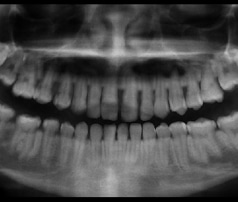

Panoramic X-ray

An X-ray taken by a machine that rotates around your head to give your orthodontist a picture of your teeth, jaws, and other important information.